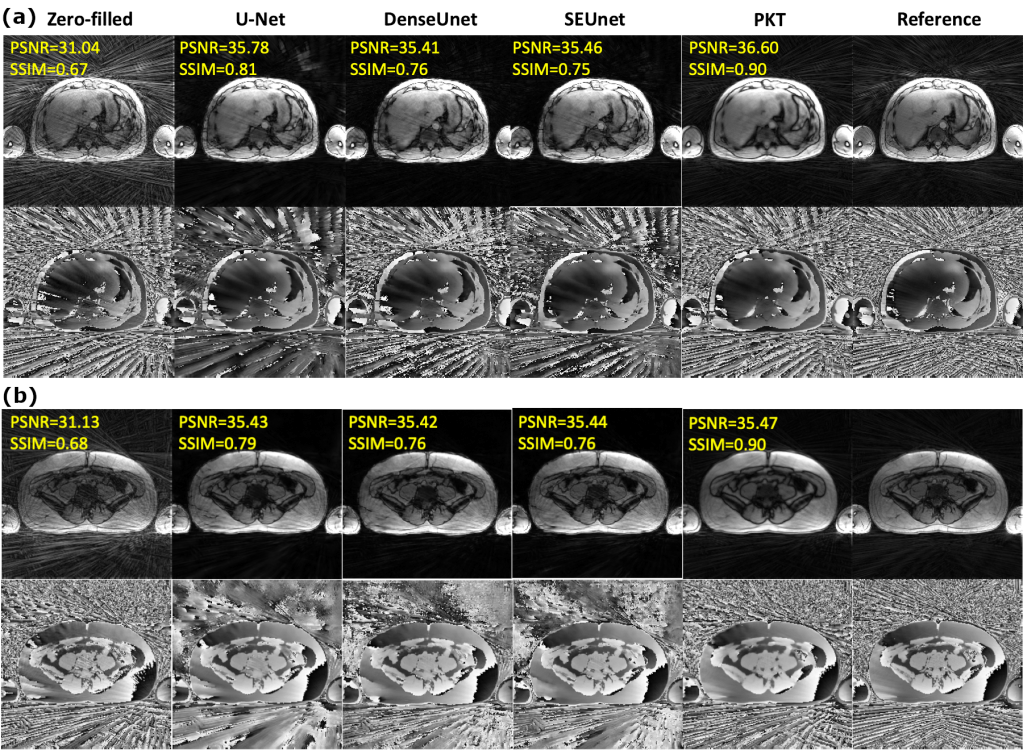

- Proposed to rearrange the radial spokes to sequential data based on the chronological order of acquisition

- Developed a projection-based k-space transformer network (PKT) to predict unacquired k-space data

- Achieved 4× acceleration of 2D radial acquisition and state-of-the-art performance